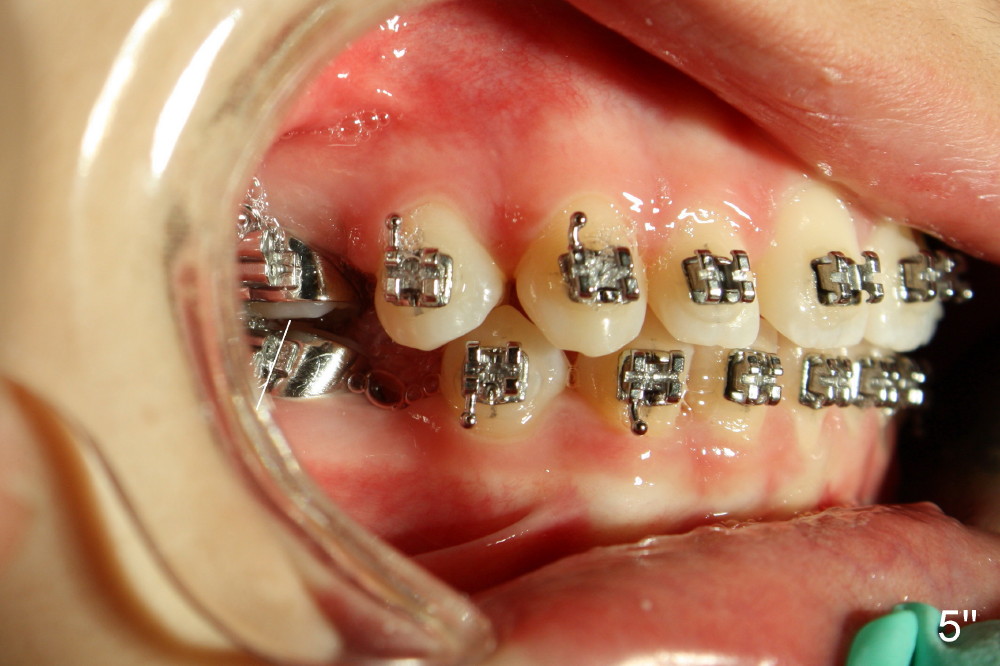

A 13-year-old Asian girl seeks orthodontic treatment for crowding. The lower 2nd bicuspids are congenitally missing (Fig.1,8), whereas the upper right one rotates 180° and the upper left is partially impacted (Fig. 1, 7). The lip muscles strain when the lips close (Fig.3). Orthodontic treatment started with extraction of four affected teeth (#4,13, K and T) 6 months ago. .018' niti wires are being used. Dental midlines do not coincide preop and intraop (Fig.4,4'). Pre-op front view shows that the upper dental midline coincides with the facial one (Fig.1'). There is Class I canine and molar relationship on the right (Fig.5,5',9,9'); open bite on the left (Fig.6,6',10,10').

Update: The left open bite was closed less than one month by wearing elastics between upper and lower teeth (Fig. 6'''). The occlusal plane and midline improve (Fig.4''). Wires have gradually changed to .016x.016, .016x.022 and now .018x.025 with power chains. All the spaces are closed except the one in LR (Fig.7''-10''). What I cannot accomplish is to fix meisal (Fig.5'' (white line), 9'') and lingual (Fig.8'' arrows) inclination of LR molars, although elastic is instructed to be placed between UR7 buccal and LR7 lingual. The rectangular wires could be twisted to fix lingual inclination. Which should be done first: LR space or LR molar inclination? Click each figure for magnification.